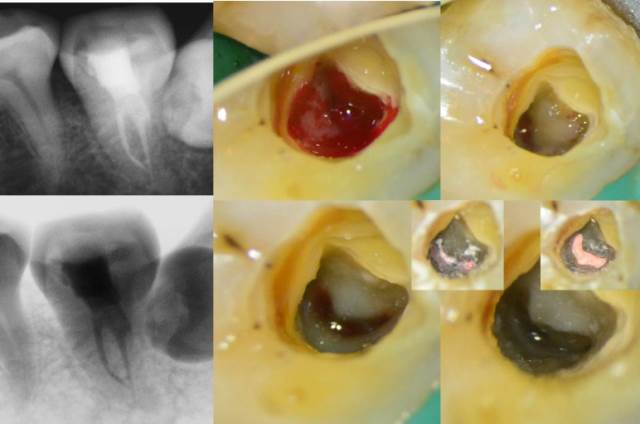

图:我科全面开展国际化显微治疗

显微根管治疗是我们的看家本领,这里也是省内根管治疗的终点站,我们科的显微牙医们用专业、极致的技术处理了各类疑难根管,比如取根管断针、疏通根管钙化以及牙髓反复治疗失败病例的再治疗,专业处理各类根管治疗并发症和后遗症。并且开展了国际前沿的治疗项目——显微根尖手术、牙髓血运重建术/牙髓再生术,最大限度地为患者保存自身牙齿组织。

科室全面开展显微牙体牙髓一体化治疗,由根到冠一站式解决整颗患牙的治疗需求。以患牙的功能为目的设计治疗方案,在完善根管治疗后即时进行牙冠缺损的修复,包括直接充填、嵌体/全冠修复等,保证根管治疗的疗效。最大限度地节省患者的治疗时间,减少复诊次数,并提高治疗的成功率。

图:牙体牙髓冠根一体化治疗方案,一站式解决患者牙体及牙髓病的治疗需求